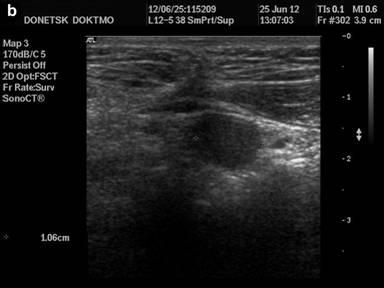

Ultrasound diagnostics (Figure 2а, b): no free fluid in the abdominal cavity and pleural sinuses. Liver: total size (left and right lobe) - not increased, smooth circuit, capsule is not thickened, no signs of hepatoomentopexy, total echogenicity - normal, no focal changes. Portal vein - 0.9 cm in diameter, blood velocity 24.0-30.0 cm/s, hepatopetal undulating blood flow. Hepatic artery: blood velocity - to 80.0 cm/s, low-resistant type of blood flow. Induration of the round ligament of the liver with the presence of effect of distal attenuation from it, without signs of recanalization. Gall bladder - common anatomical location, form, circuit, volume; wall - not thickened. Choledochus - 0.3 cm in diameter. No concrements. Pancreas - no liquid collectors in the projection of omental bursa, total volume is not increased, smooth circuit, echogenicity is slightly increased, in the projection of the cervix - body not dilated Wirsung’s duct is visualized (0.2 cm in diameter). Spleen - rejected. Closer to the anterior abdominal wall, near the border of the parietal peritoneum - 3 solid rounded formations, transversely located in the epigastrium, at the distance of up to 2.0 cm apart from each other, hypoechoic, with a smooth circuit, homogeneous structure, upon energy mapping at the "noise" border - with single loci of blood flow, moderately movable during instrumental palpation, movable upon respiratory excursion. Kidneys, adrenal glands - without visible pathological changes.

Figure 2 а, b. Ultrasound diagnostics of the organs of abdominal cavity. Closer to the anterior abdominal wall, near the border of the parietal peritoneum - 3 solid rounded hypoechoic formations, transversely located in the epigastrium, with smooth circuits, homogeneous structure. |